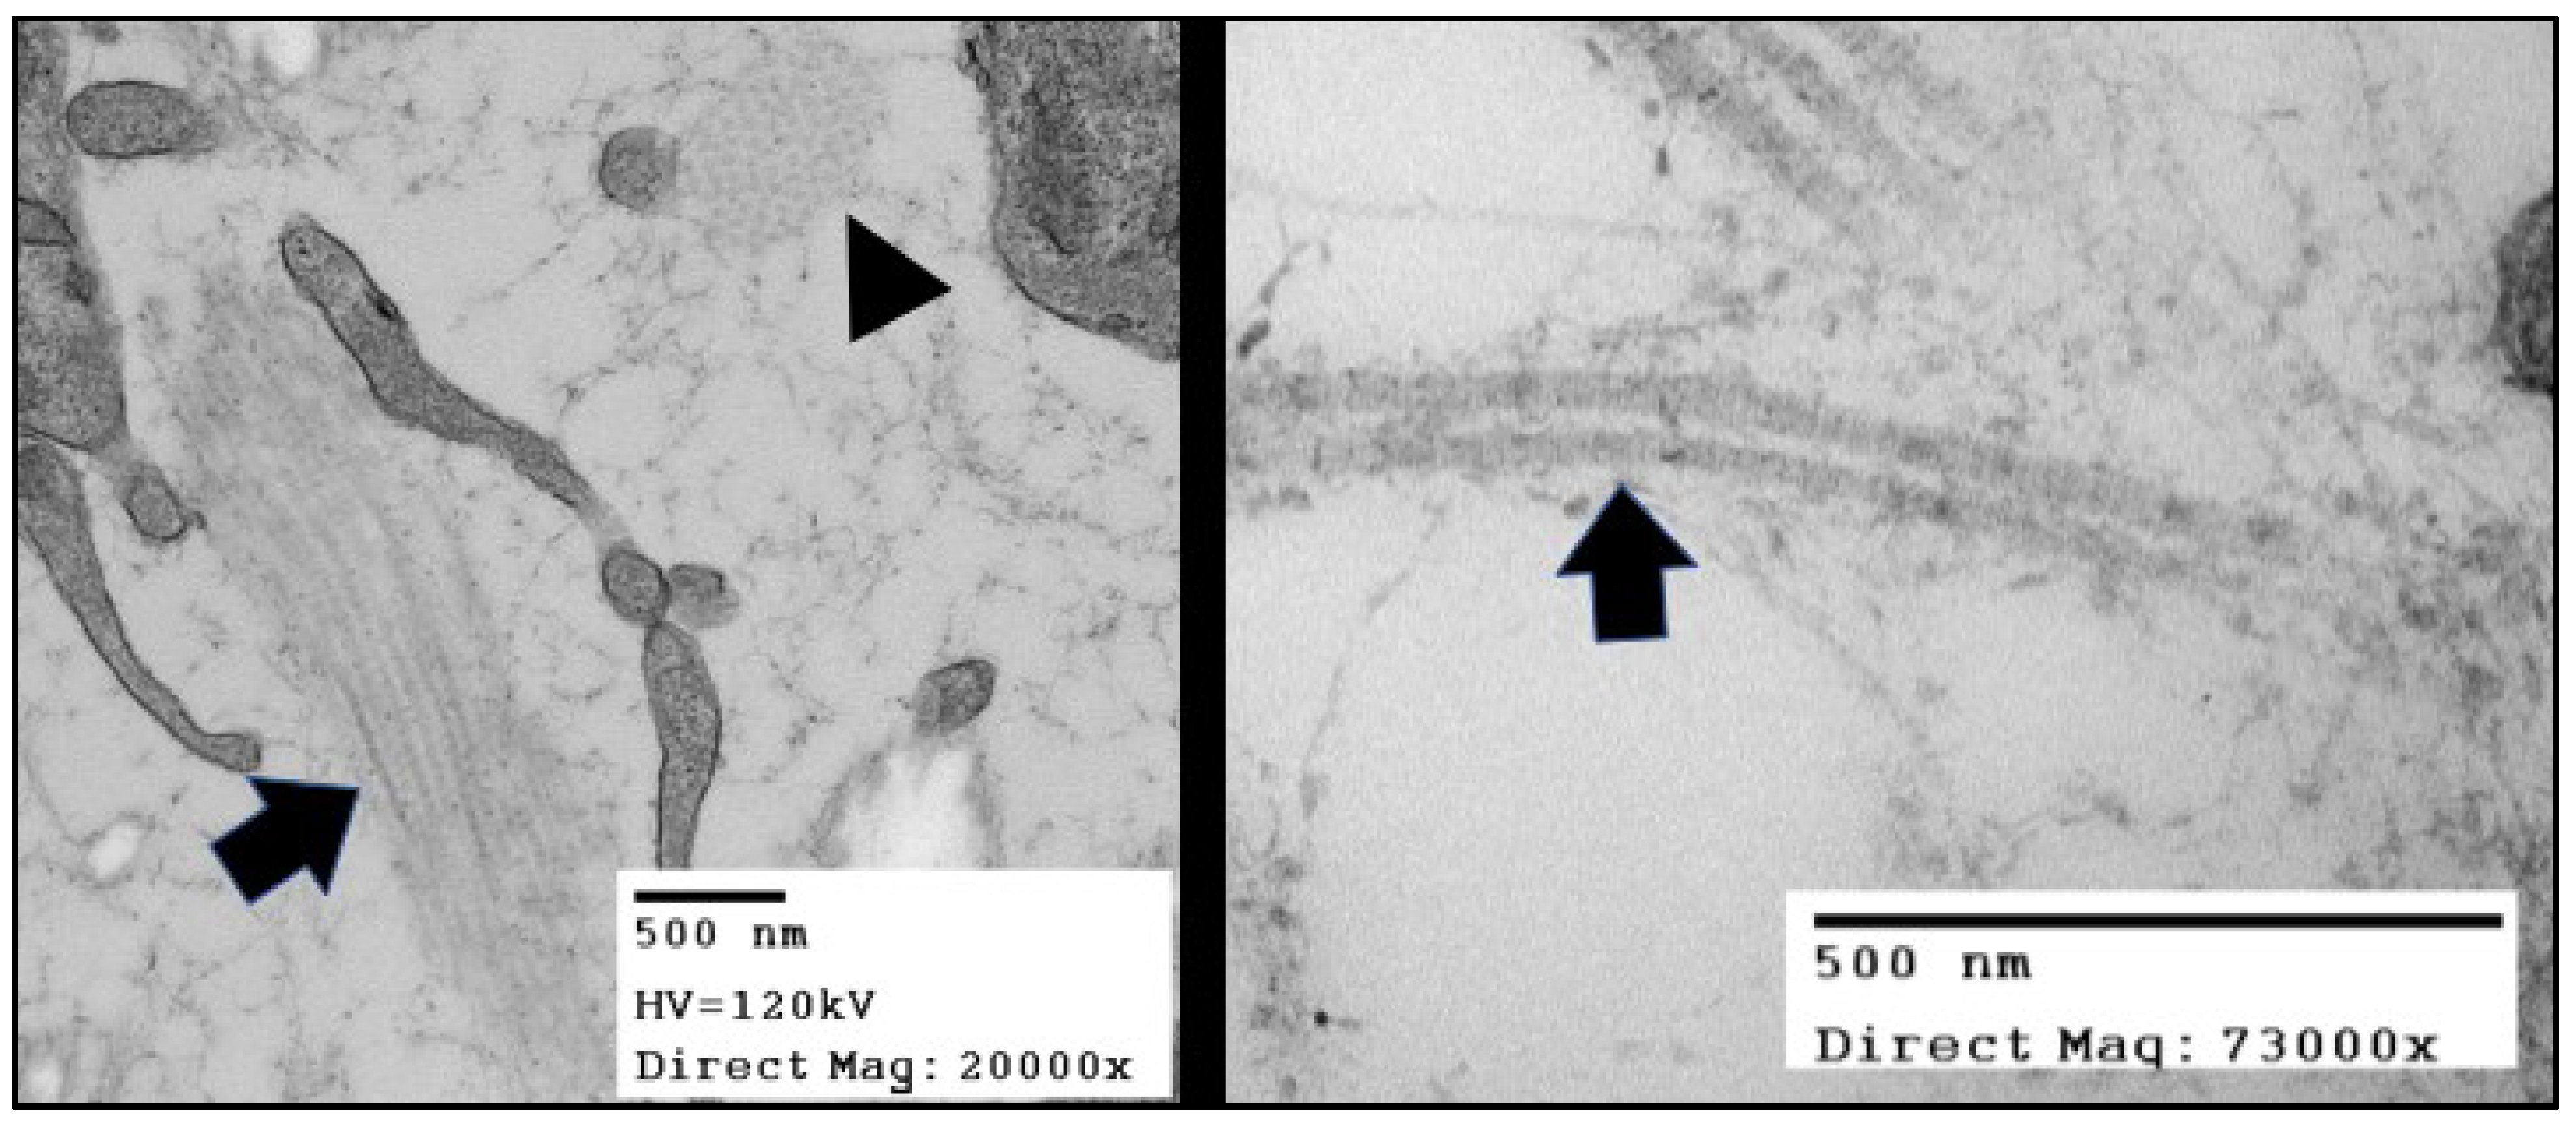

:1. Collagen in the Mitral Valve

2. Collagens, Fibrils, and Fibers of the Mitral Valve